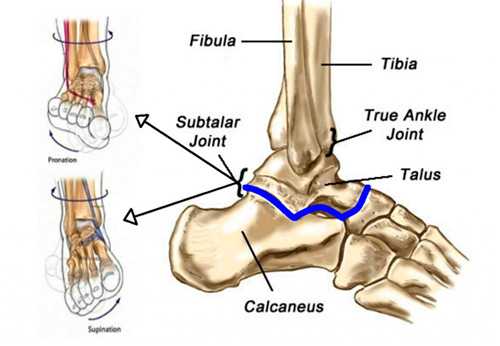

Рис. 1. Пронация и супинация стопы, подтаранный сустав, вид снаружи

Подтаранный сустав образован двумя костями: таранной и пяточной. Таранная кость имеет в своем составе тело, или задний отдел и головку или передний отдел. Между передним и задним отделами находится шейка кости. Верхняя часть тела образует блок, который контактирует в голеностопном суставе с большеберцовой и малоберцовой костями. Спереди головка тарана сочленяется с ладьевидной костью. На нижней поверхности таранной кости есть суставные фасетки: передняя, медиальная и задняя, самая большая из всех фасеток. Она отделена от медиальной и передней фасеток бороздой. Фасетки являются суставными поверхностями, которыми таранная кость сочленяется с пяточной костью. Пяточная кость состоит из тела или задней части и переднего отростка или передней части и отростка, который поддерживает таранную кость. На отростке есть суставная поверхность для контакта с кубовидной костью. На отростке сверху расположена верхняя и средняя суставная поверхность. На теле кости находится задняя суставная поверхность, самая большая по размерам. Между суставными поверхностями пяточной кости расположена глубокая борозда. Сустав может состоять из трех или двух фасеток, что является наиболее частым вариантом, который встречается в почти в половине случаев. Фасетки могут сливаться в одну или могут быть разделены бороздой, которая имеет разную глубину. Описаны случаи асимметричного строения фасеток сустава слева и справа. Между таранной пяточной костями находится тарзальный синус. Это полость конической формы, которая проходит наискось от латерального к медиальному краю стопы. По внутреннему краю стопы синус переходит в тарзальный канал, который оканчивается рядом с поддерживающим отростком пяточной кости и содержит связки. Это межкостная таранно-пяточная связка, шейная связка, передняя таранно-пяточная связка, латеральная таранно-пяточная связка и нижний ретинакулум разгибателей. Связки отделяют фасетки таранной кости друг от друга, поддерживают дистанцию между таранной и пяточной костями, препятствуют супинации в подтаранном суставе, больше, чем пронации, обеспечивают стабильность заднего отдела стопы в стоянии и при движении, удерживают таранную и пяточную кости от смещающих усилий, которые действуют на пятку снаружи внутрь. Шейная связка - самая прочная из связок, которые соединяют таранную и пяточную кости, ограничивает инверсию заднего отдела стопы. Ретинакулум удерживает сухожилия разгибателей и препятствует их избыточному натяжению, ограничивает инверсию заднего отдела стопы. Наибольшая подвижность блока таранной кости в вилке голеностопа отмечается в положении стопы между нейтральным и углом сгибания 15°.